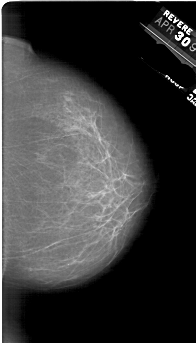

A_1865_1.LEFT_MLO

LEFT_MLO LINES 6016 PIXELS_PER_LINE 4021 BITS_PER_PIXEL 12 RESOLUTION 43.5 OVERLAY